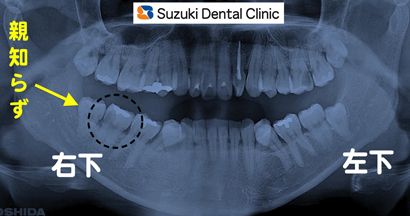

30代の女性。主訴は「親知らず辺りが痛い」でした。

〈レントゲン〉

親知らずの隣りの歯が、大きな虫歯になっていました。痛みを止めるためにも神経を抜かなくてはなりません。親知らずの抜歯と同時に行ないました。 続きを読む